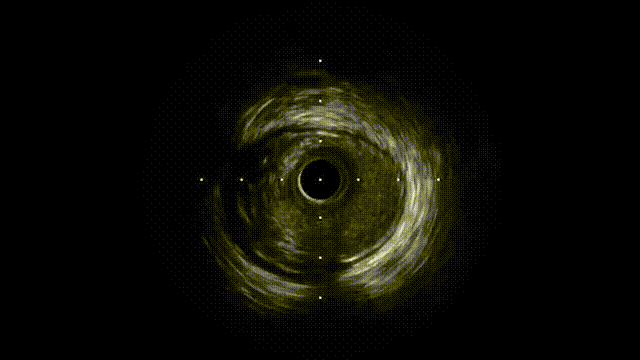

IVUS确诊夹层特征(图1F-G,视频3):

真腔受假腔压迫,假腔延伸至钙化斑块深部

LAD开口内膜撕裂,左主干未见明显夹层

F-G. IVUS:真腔受压,假腔延伸至钙化后方,内膜撕裂(黑色箭头)